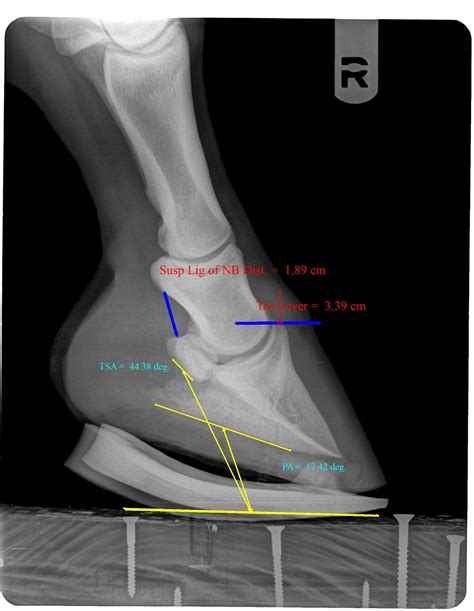

Navicular bone | Anatomy.app